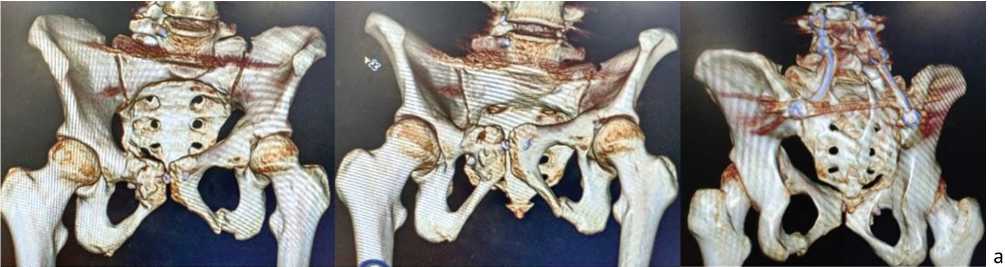

Результат более 85 баллов по шкале Majeed (международная шкала отдаленных результатов хирургического лечения нестабильных повреждений костей таза и крестца) является отличным. Мы планируем удалить металлоконструкции. На компьютерных томограммах таза через шесть (рис. 5) и 12 мес. после операции (рис. 6) определяли консолидацию переломов таза и крестца, металлоконструкции стабильны.

Рис. 5. Компьютерные томограммы таза, шесть месяцев после операции: а — 3D-реконструкции

Рис. 5 (продолжение). Компьютерные томограммы таза, шесть месяцев после операции: б — сканы во фронтальной и сагиттальной проекциях